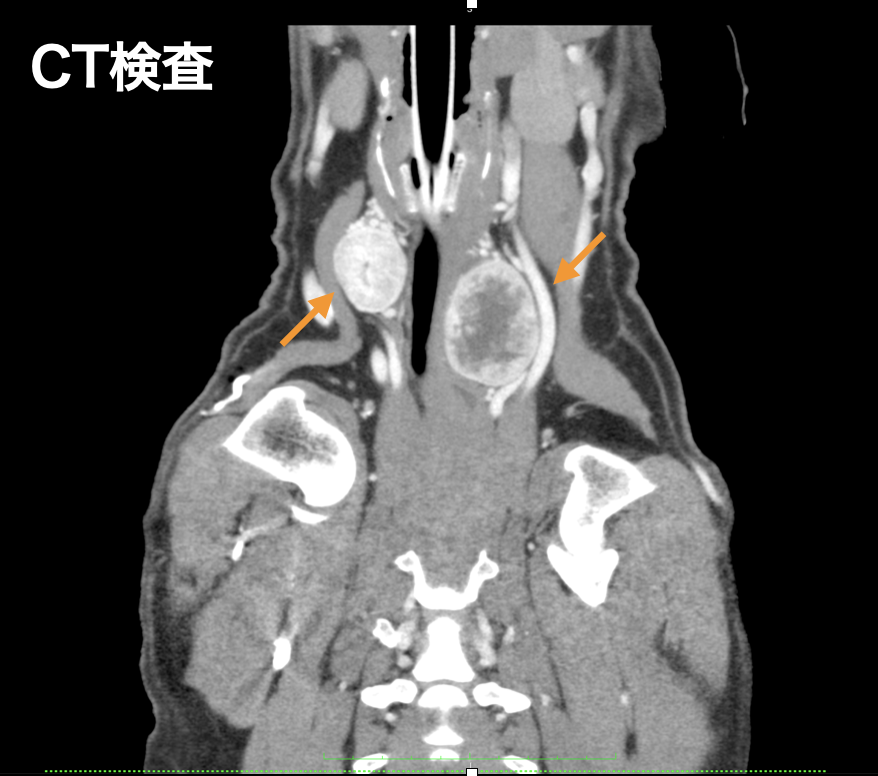

10歳、雑種犬、去勢雄のワンちゃんが、両側の頸部腫瘤(甲状腺腫瘍疑い)の精査のため来院されました。CT検査、細胞診検査にて、リンパ節転移や遠隔転移を認めなかったため、甲状腺腫瘤の摘出を計画しました。手術合併症として、甲状腺機能低下症、低カルシウム血症、反回喉頭神経麻痺などがあります。そのため左右一度にではなく、約1ヶ月の期間をおいて段階的に切除をすることにしました。幸い外上皮小体の温存が可能であり、重篤な合併症もなく退院いたしました。